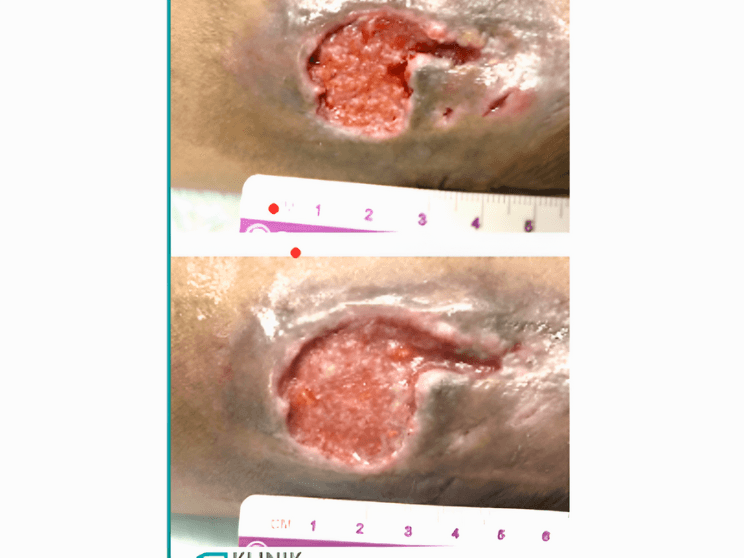

This was the case for a 70-year-old man who had a history of stroke and paralysis. Spending long hours lying down caused an open sore to develop in his buttocks area. The wound appeared red, moist, and at high risk of infection—prompting immediate and consistent care.

Day 12–18: Visible Signs of Healing

By day 12, the ulcer looked cleaner and less inflamed. By day 18, the wound showed clearer signs of tissue regeneration. Redness decreased, and the surface looked healthier and drier.